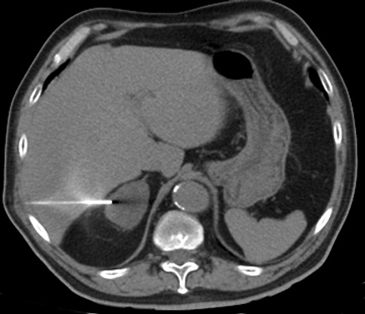

e) Biopsia percutánea guiada por TAC

En la actualidad su uso es excepcional y su indicación esta reservada para casos en que las técnicas no invasivas no son diagnosticas y en casos en que se sospecha un linfoma y es necesario tipificarlo. En el lado derecho si la masa es pequeña se prefiere el abordaje transhepático (Figura 16 a) y en el lado izquierdo la vía dorsal posterior (Figura 16 b).

La vía transhepática sólo se realiza con aguja fina, de manera que si en el lado derecho es necesario obtener mayor cantidad de tejido, la biopsia se realiza con una aguja de tipo trucut pero el acceso tiene que ser por vía dorsal posterior.